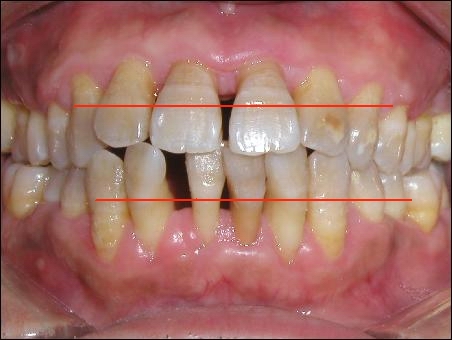

患有牙周病的牙

正常的牙齦應(yīng)該在紅線的位置,但現(xiàn)在已因牙周病而萎縮。牙齒顯得很長,那些黃色的印記,是原來牙齦所在的位置,而現(xiàn)在,它就像河水干涸之后,裸露的巖石,標(biāo)志著一個(gè)人歷經(jīng)的歲月滄桑。牙醫(yī)們經(jīng)常會(huì)告訴你一句話,被吸收的牙槽骨是不可能再生長的。換言之,一旦牙槽骨被吸收了,這個(gè)過程是不可逆的。但事實(shí)上,人的骨骼就像人的肉一樣,在一定程度上是可以再生的。當(dāng)然我的意思并不是說,把腿砍了,可以再長出一條腿,而是說,如果你骨折了,斷了的地方是會(huì)接上的。而且接上的地方甚至比沒有斷過的地方長的還結(jié)實(shí)。其實(shí)長上的并非是骨頭,而是被一些類骨組織,像膠原蛋白形成的組織包裹住了,就像樹上長的結(jié)子一樣。因此,凡是得了牙周病的人,基本可以肯定地說,他體內(nèi)的蛋白質(zhì)開始慢慢變少。而蛋白質(zhì),是組成生命活動(dòng)最基本的組織---細(xì)胞中,除水以外的最主要物質(zhì)。人體的衰落,從牙齒上可以略見一斑。